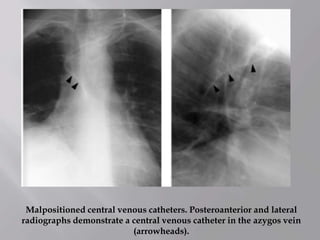

Malpositioned central venous catheters. Posteroanterior and lateral

radiographs demonstrate a central venous catheter in the azygos vein

(arrowheads).